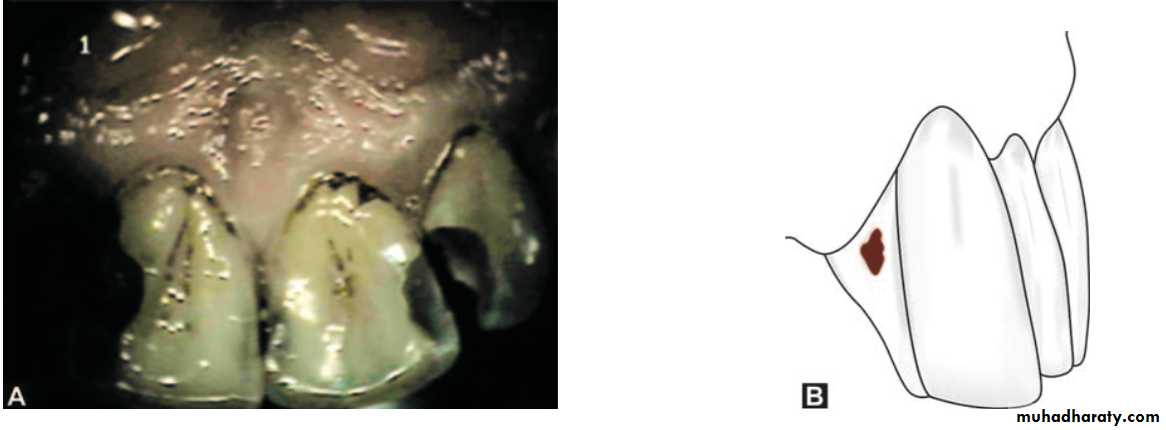

Preparations on gingival third of facial and lingual or palatal surfaces of all teeth came under Class VClass VI